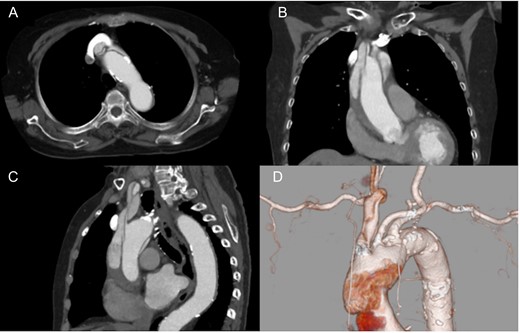

An 86-year-old woman with acute type A aortic dissection was transferred to our institution. Contrast enhanced computed tomography (CT) showed aortic dissection involving the ascending aorta extending to the proximal descending aorta. The true lumen of the brachiocephalic artery was occluded by the false lumen (Fig. 1). No neurological symptoms were present preoperatively. The patient was transferred to the operating room, and underwent central aortic repair with ascending aortic and bicaval cannulations. Cerebral perfusion was monitored with near-infrared spectroscopy (INVOS cerebral oximeter, Somanetics Inc, Troy, USA) and transcutaneous carotid echo. Inside the aorta, the orifice of the brachiocephalic artery was completely occluded by the false lumen. Selective cerebral perfusion (SCP) through the brachiocephalic artery was initiated immediately, however, the SCP flow was not sufficient due to stenotic lesion with low right side regional oxygen saturation (rSO2). Considering low rSO2, it was felt that the lesion should be treated even without preoperative neurological symptoms. The S.M.A.R.T. Vascular Stent System (Cordis Corp, Fremont, CA, USA) (12 mm × 40 mm) was inserted and deployed inside the brachiocephalic artery. After SCP cannula was inserted through the stent, right side rSO2 increased similar to the left side. Finally, ascending aortic replacement by using 26 mm J-Graft (Japan Lifeline Co., Ltd., Tokyo, Japan) was performed. Postoperative course was uneventful without any neurological event. Postoperative CT scan showed good stent patency and no residual dissection in the brachiocephalic artery (Fig. 2).

Preoperative computed tomography findings. Axial (A), coronal (B) and sagittal view (C). 3D computed tomography angiography (D). The brachiocephalic artery was occluded by the false lumen.